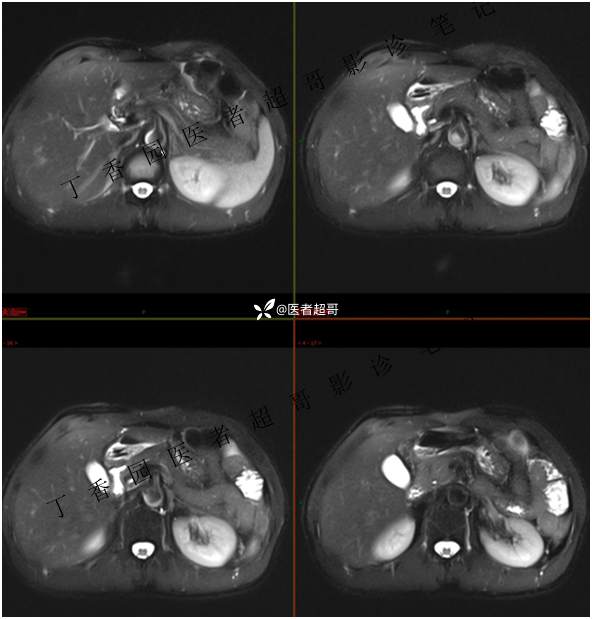

肝胃间隙肿瘤,间质瘤?平滑肌瘤?还是鞘瘤?有结果,请分析!

现病史:患者于3天前查体行肝胆脾胰肾彩超示肝内实性占位,无恶心、呕吐,无发热、寒战,无腹胀、腹泻,进一步于医院行上腹部CT增强示:肝胃交界处肿块。未行特殊治疗。今患者为求进一步治疗,来我院就诊,门诊以“肝占位性病变”收入院。患者自发病以来,神志清,精神可,饮食睡眠可,二便可,体重近期未见明显变化。